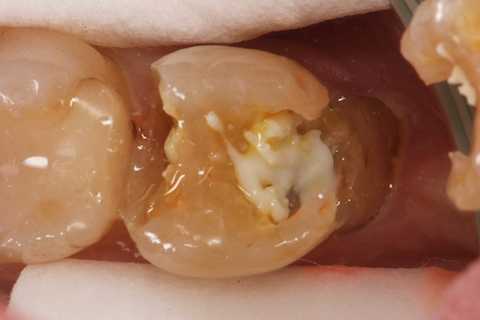

この症例は歯根内部をいじられていないので、根管治療は難しくない。CRで歯冠を再建するのが難しかった。

再建が終わった後で、内部の治療をしてCRで埋め戻している。